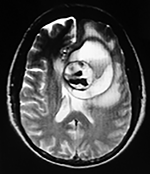

EJEMPLO DE CASO CLÍNICO (9)

Paciente masculino de 34 años de edad, quien presenta crisis convulsivas parciales motoras de brazo y hemicara derecha, secundariamente generalizadas, posteriormente hemiparesia 4/5 para hemicuerpo derecho.

La TAC muestra un área hiperdensa a nivel frontal izquierdo heterogénea que no refuerza con medio de contraste.

LA RMN muestra una lesión bien circunscrita frontal parasagital izquierda con edema perilesional, hiperintensa en T1 y T2, de contenido sólido y quístico, con poca captación del medio de contraste.

Se realizó craneotomía frontal para abordaje interhemisférico anterior.

Se realiza resección total de la lesión de contenido hemático oscuro-verdoso, consistente en un angioma cavernoso. La RMN postoperatoria se observa solo la brecha quirúrgica sin evidencia de lesión.

En el postquirúrgico el paciente desarrollo síndrome frontal lateral, que se controló con Risperidona y remitió después de tres semanas, las crisis convulsivas remitieron y el medicamento se disminuyó de manera paulatina (figs. 4 y 5).

Figura 4:

Imágenes prequirúrgicas y postquirúrgicas de lesión multiloculada del caso 9.